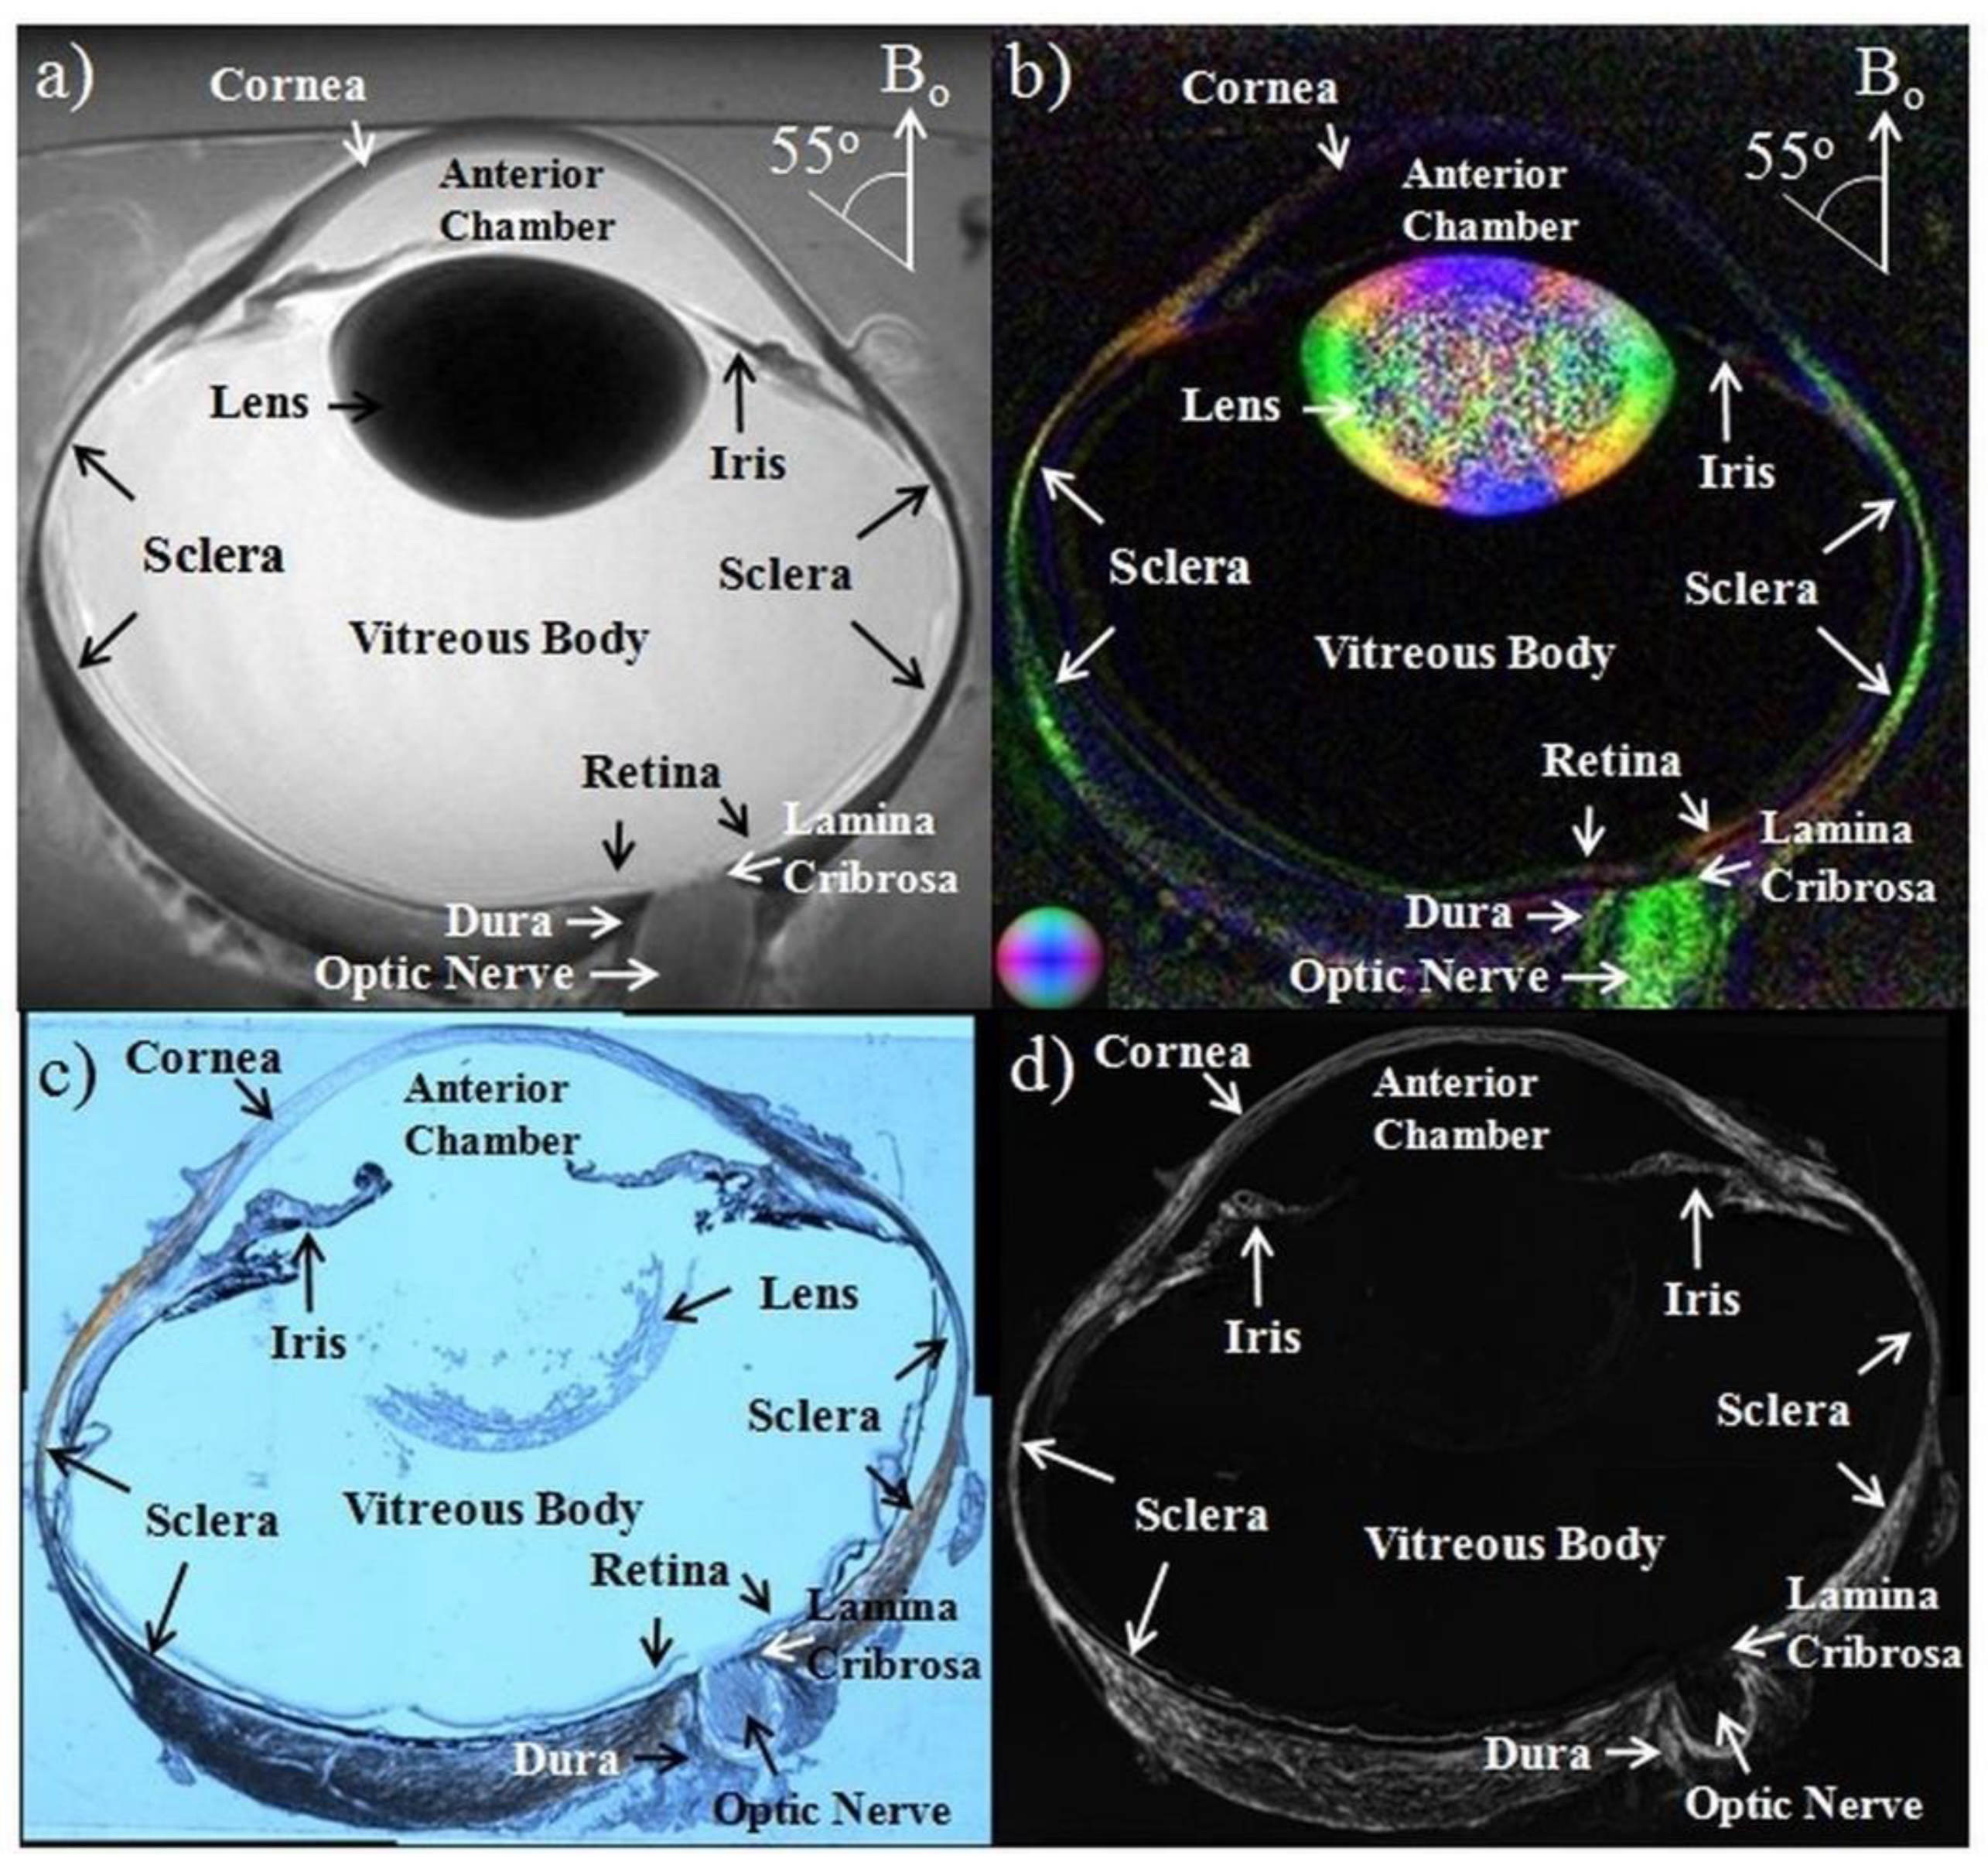

2.2. Anatomical MRI in Glaucona

- Ho, L.C.; Sigal, I.A.; Jan, N.-J.; Yang, X.; Van Der Merwe, Y.; Yu, Y.; Chau, Y.; Leung, C.; Conner, I.P.; Jin, T.; et al. Non-invasive MRI Assessments of Tissue Microstructures and Macromolecules in the Eye upon Biomechanical or Biochemical Modulation. Sci. Rep. 2016, 6, 32080. [Google Scholar] [CrossRef]